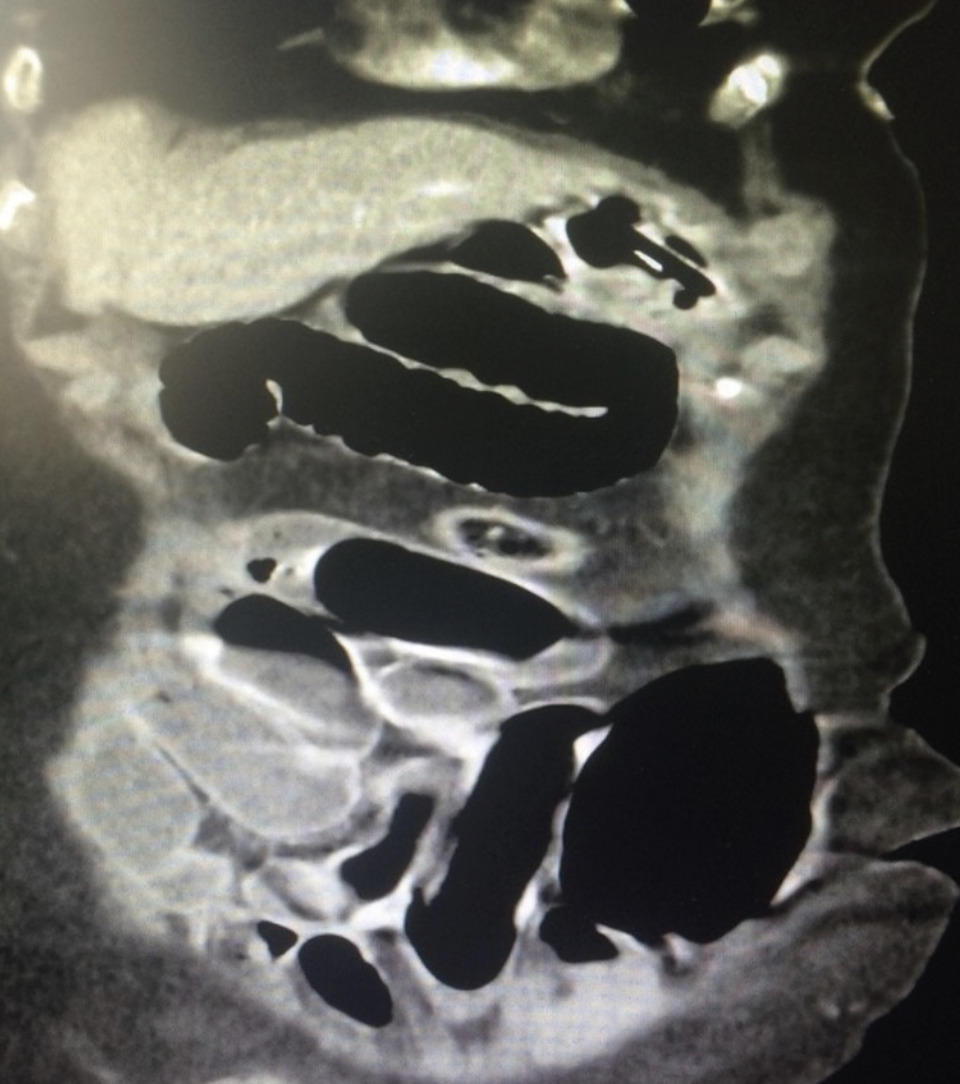

Devant ce tableau fortement évocateur d’un syndrome occlusif, le scanner abdominopelvien injecté par produit de contraste iodé met en évidence un syndrome occlusif grêlique sur un iléus réflexe dû à une appendicite aiguë incarcérée dans une hernie inguinale droite directe, avec distension et stase liquidienne de toutes les anses grêles en amont et de l’estomac, sans signe de souffrance pariétale digestive (fig. 1 et 2).